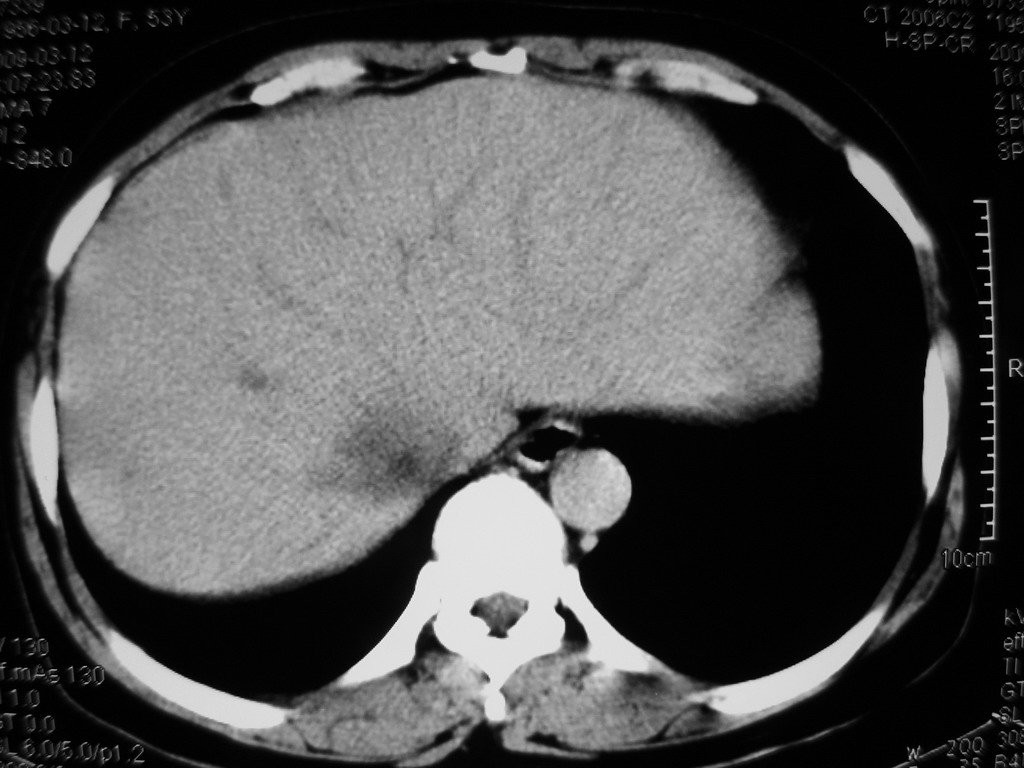

患者,女性50岁,上腹部不适2年余,既往多次腹部彩超未见异常,今日上午在我院查彩超发现肝右叶囊实性病变,外院辅助检查,afp,cea,ca199, 都在正常范围内,无肝炎史否认肿瘤史,生活在牧区

接着往下一贴看,有静脉期和延迟期,在看看和下腔静脉及十二指肠的关系,腔静脉内是不是栓子?

考虑肝右叶与尾叶交界区肝癌(部分外生),侵犯下腔静脉并下腔静脉瘤栓形成。